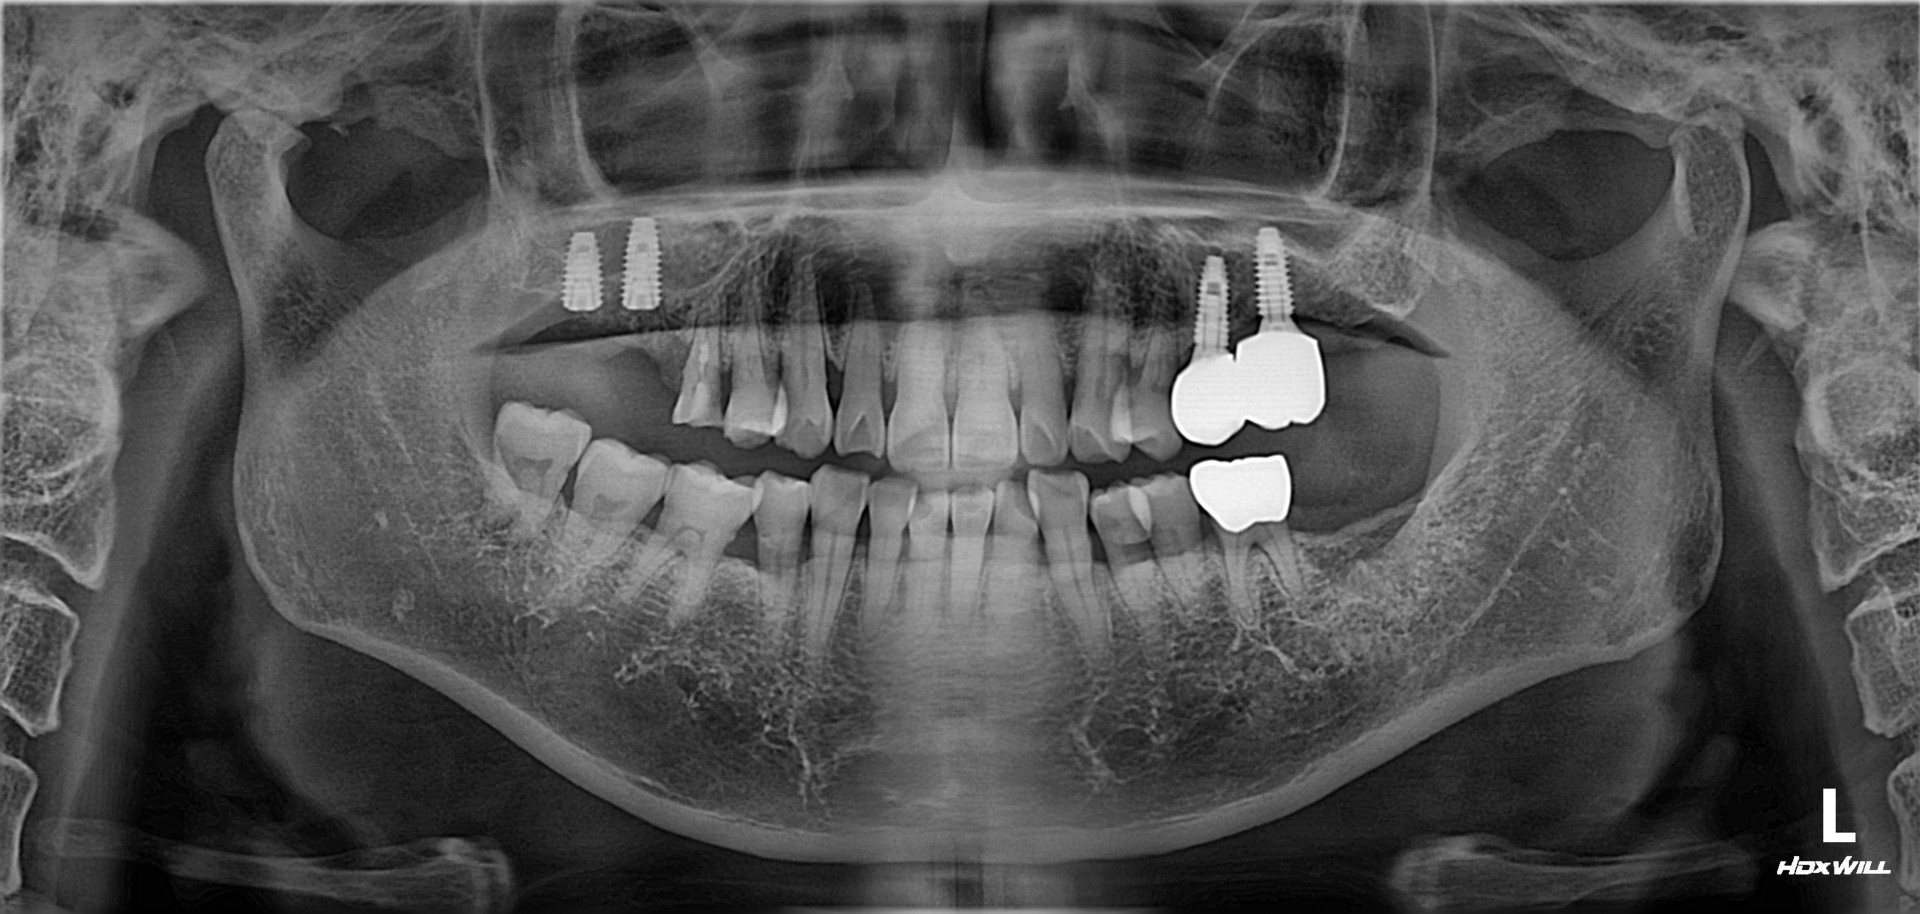

상악동 거상술 및 임플란트 식립

치료 기간 2023. 12. 21(치료 당일)

아래 치료는 상악동 거상술 및 임플란트 식립에 대한

치료 당일에 대한 설명입니다.

우측 상악 잔존골이 얼마 없는 난이도가 있는 수술이지만, 참조은치과에서는 수술시간이 15분 정도 소요되었습니다. 근육주사를 이용하여 붓기 조절 및 염증 조절도 시행하였습니다.

아래 치료는 상악동 거상술 및 임플란트 식립에 대한 치료 당일에 대한 설명입니다.

우측 상악 잔존골이 얼마 없는 난이도가 있는 수술이지만, 참조은치과에서는 수술시간이 15분 정도 소요되었습니다.

근육주사를 이용하여 붓기 조절 및 염증 조절도 시행하였습니다.